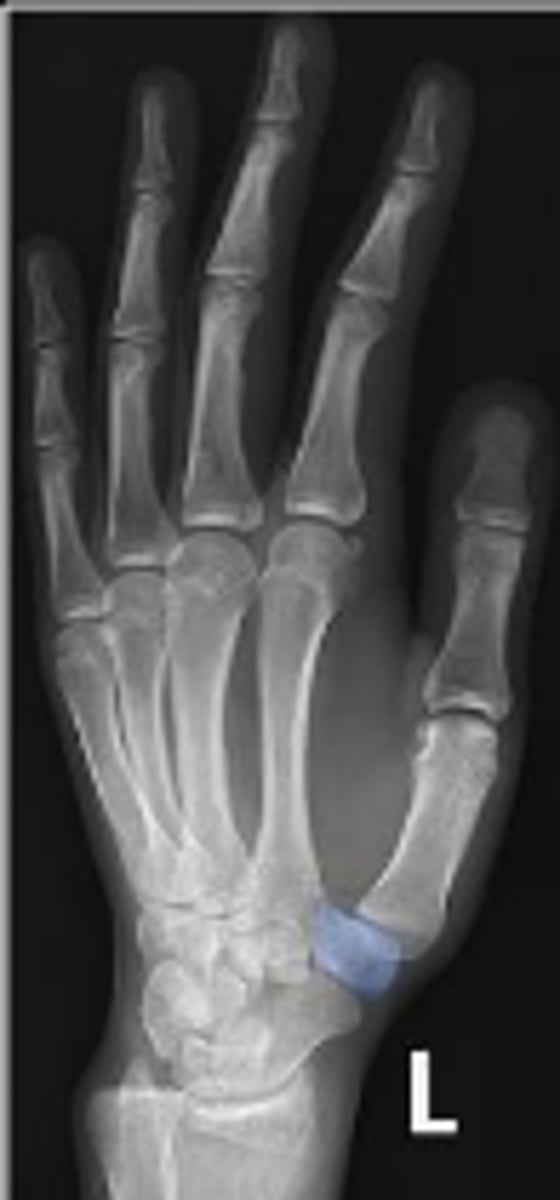

Medial oblique of the left wrist

What is the name of the radiographic view?

Hook of the left hamate

What is outlined?

Left hamate

Left lunate